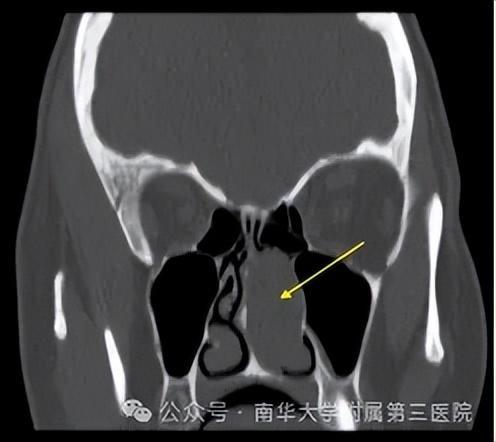

医生通常可通过前鼻镜检查或鼻内窥镜伸入鼻腔拍照进行检查,该检查可发现鼻腔内或中鼻道荔枝状透明的息肉样新生物或鼻甲部分组织息肉样变,或者通过鼻窦CT检查来诊断。

(▲通常基于患者的症状、鼻腔检查以及影像学检查,如鼻窦CT扫描,后者可以帮助确定息肉的大小和位置,以及是否伴有鼻窦炎)